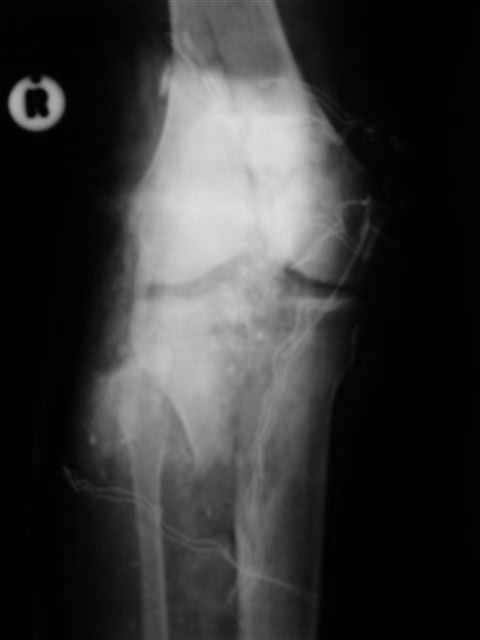

№4 снимок через два дня после операции, супракондилярный перелом, при поступлении конечность была холодная и без пульса, подозрение на повреждение сосудов, сделана ABI (ankle-brachial index) в приемном отделении, индекс меньше 1 к 0.9 в норме 1 к 1.1, срочная ангиография в операционной после Ex-Fix, по два стержня в сегменте наложен в течение 20 мин, повреждение подколенной артерии, ушивание сосудистым хирургом через медиальный доступ в дистальном отделе бедра и двухразрезная профилактическая фацсиотомия, перкутанная фиксация каннюлированными шурупами несмещенного перелома шейки бедра и дополнительные стержни в фиксаторе для жесткости.